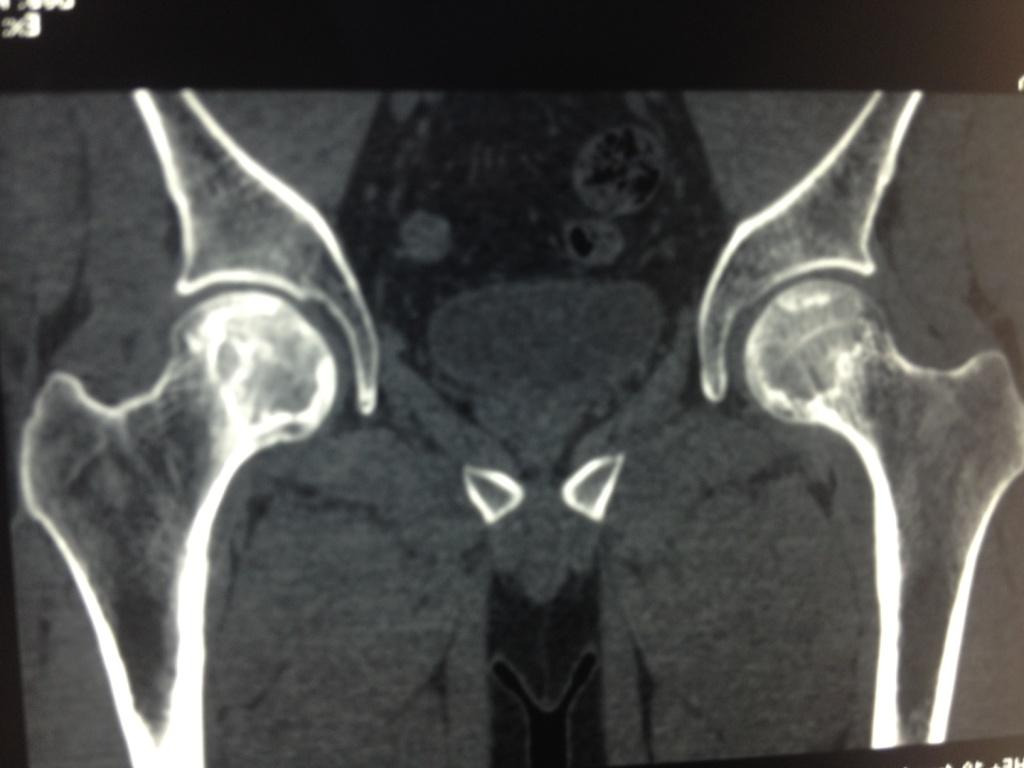

Пациента,32 лет.беспокоят боли в левом тазобедренном суставе. Болеет около 2 лет. Клинически - незначительные боли и ограничение ротации. Данные Рент, КТ, МРТ прилагаются